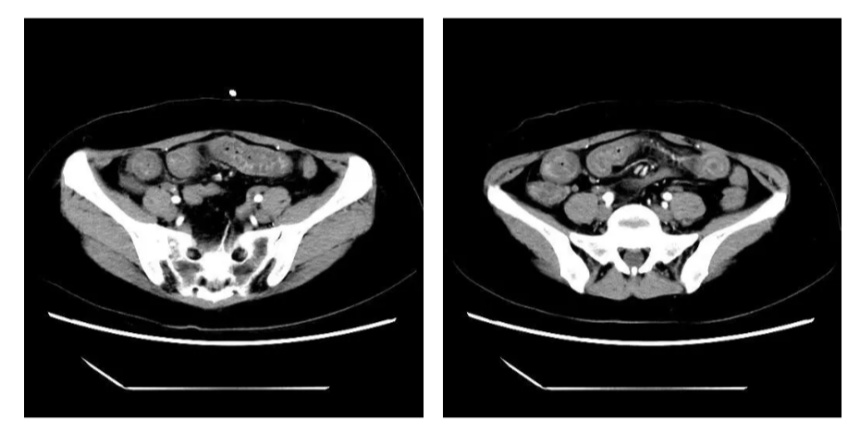

又是一个繁忙的工作日,病房里一如既往的人声鼎沸。一位40岁的女性患者,在家属的陪同下匆忙的进入到诊室,诉说着自己的痛苦经历:5天前她和小伙伴聚餐进食了少许生食,2天后就出现脐周及上腹部阵发性隐痛,还伴随着恶心、呕吐,就近在附近医院就诊考虑急性胃肠炎,抗感染后症状缓解不明显,后转诊到复旦大学附属华东医院急诊查小肠增强CT见到小肠广泛的增厚、水肿,周围有渗出样改变,症状反复出现,患者无法进食,极度折磨。

于是第一时间收入病房,完善了一系列检查,考虑小肠炎症,予禁食、抗感染、营养支持后症状逐步好转,在治疗过程中,考虑到随访过程中若反复进行CT检查存在一定顾虑,于是在入院时和症状好转后分别进行了肠道超声检查,来帮助医生们评估肠道炎症的情况。

入院时患者的肠道超声报告提示:

•小肠5区肠壁增厚,Limberg I,肠系膜周围见多发肿大淋巴结;

•小肠6区肠壁增厚,Limberg I,盆腔内、小肠周围见少量积液;

•升结肠、横结肠、降结肠、乙状结肠未见明显异常。

在进行治疗、患者症状基本消失后复查了肠道超声,上述节段的小肠炎症基本在超声下都消失了,再加上患者症状也基本消失,医生们在治疗上进行了调整,逐步开放了饮食,同时进行了其他一系列的检查明确了诊断,患者也平稳出院了,近期随访下来患者没有出现症状反复,生活状态良好。